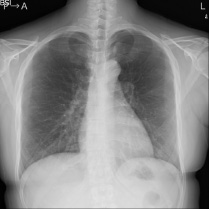

一般撮影

- ・平面の撮影をします。

- ・骨折や病変が存在するかの検査時に使用します。

一般撮影の撮影画像

骨の画像

胸の画像